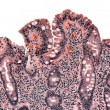

Rak szyjki macicy wykryty we wczesnym stadium jest niemal całkowicie uleczalny. Cytologia ginekologiczna to bezbolesne badanie, wykonywane podczas wizyty u ginekologa, które pozwala odpowiednio wcześnie wykryć i zacząć terapię tego nowotworu. Stany przednowotworowe w ciągu kilku lat przekształcają się w nowotwór szyjki macicy, dlatego cytologia pozwala na wykrycie nie tylko samych komórek rakowych, ale i stanów przedrakowych.

W odróżnieniu od klasycznej cytologii, w cytologii zwanej LBC (Liquid Based Cytology), możliwość zaistnienia powyższych sytuacji ograniczona jest do minimum.Jest to możliwe dzięki temu, że cienkowarstwowy wymaz z szyjki macicy pobierany jest na specjalne płynne podłoże, które podlega dalszej obróbce laboratoryjnej w pracowni cytologicznej. Dlatego metoda ta nazywana jest cienkowarstwową.

Badanie LBCzalecane jest przez lekarzy, gdyż znacznie poprawia jakość i wiarygodność wyniku cytologicznego i minimalizuje ilość wyników nieprawidłowych lub nieczytelnych. W związku z tym nie ma konieczności powtarzania badania, co nie pociąga za sobą konieczności kolejnych kosztów i utraty czasu, a co najważniejsze, daje ogromne szanse na uniknięcie choroby. Większą czułość i dokładność tej metodyw stosunku do cytologii konwencjonalnej, potwierdziły badania kliniczne w latach 1997-2003, kiedy to przeprowadzono 14 programów, w których przebadano ponad 600 000 kobiet. Wyniki badań dowiodły, iż nową metodą wykryto o 17-223% więcej komórek atypowych (stan HSIL), w porównaniu do cytologii klasycznej.